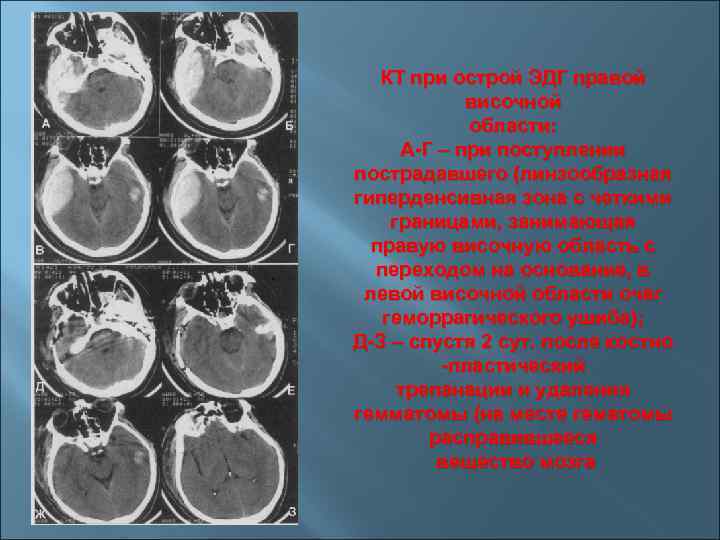

КТ при острой ЭДГ правой височной области: А-Г – при поступлении пострадавшего (линзообразная гиперденсивная КТ при острой ЭДГ правой височной области: А-Г – при поступлении пострадавшего (линзообразная гиперденсивная зона с четкими границами, занимающая правую височную область с переходом на основание, в левой височной области очаг геморрагического ушиба); Д-З – спустя 2 сут. после костно -пластический трепанации и удаления гемматомы (на месте гематомы расправившееся вещество мозга